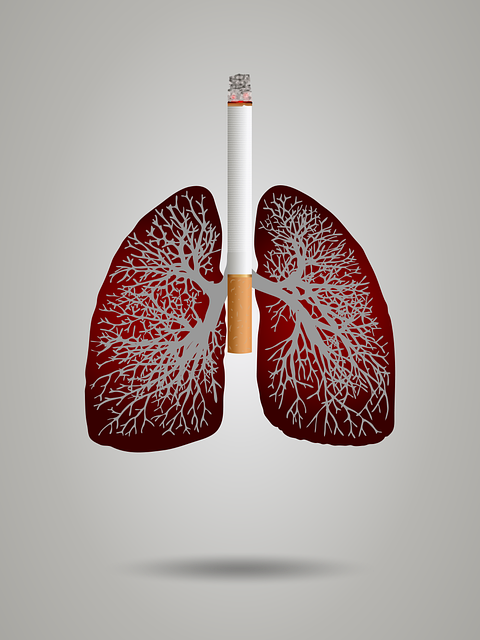

8. 흡연 , 간접 흡연

폐암 발병의 주된 원인은 흡연으로 인한 발병이 90% 이상으로 폐암 환자 10명 중 7명 이상이 흡연자로 알려져있습니다. 또한 흡연자 뿐만 아니라 간접 흡연자도 폐암에 걸리는 사례가 많아지고 있습니다. 담배를 피우지 않는 비흡연자도 전체 폐암 환자 중 30% 이상을 차지하며 흡연자가 내뱉는 연기를 비흡연자가 마시는 간접 흡연이 1.5배 이상의 폐암 발병율을 높이는 주된 요인으로 알려져 있습니다. 간접 흡연에도 유의하여 건강에 유념하도록 합시다.

말씀드렸다시피 폐암 환자 중 10명중에 평균 7명 이상이 흡연자라는 연구 결과가 있습니다. 그만큼 가장 주요 원인은 흡연으로 인한 폐암 발병이 가장 크다는 이야기입니다. 폐암은 금연으로 90% 이상 예방할 수 있으며 간접 흡연 또한 위험하오니 최대한 피해주시는 것이 좋습니다. 추가로 건강검진 비용을 아깝다고 생각하지 마시고 꼭 매년 건강검진 받으시면서 초기 예방하셔서 건강한 삶을 유지하셨으면 좋겠습니다.

1. 흡연은 피할 것 2. 간접 흡연은 피할 것 3. 미세먼지가 심한 날은 마스크 착용 필수 4. 건강검진은 필수 5. 먼지가 많은 곳에서 환기는 필수